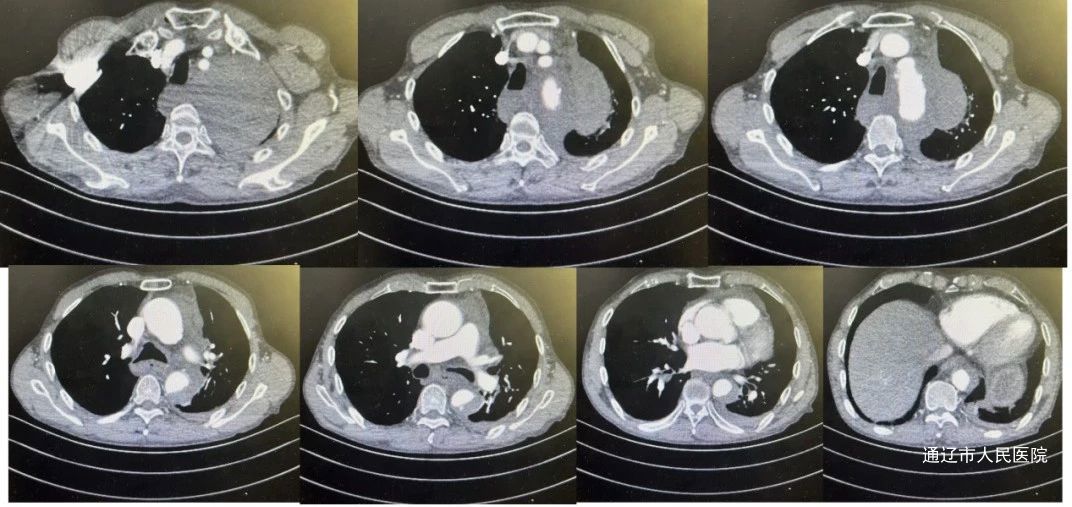

术前主动脉CTA图像与结果